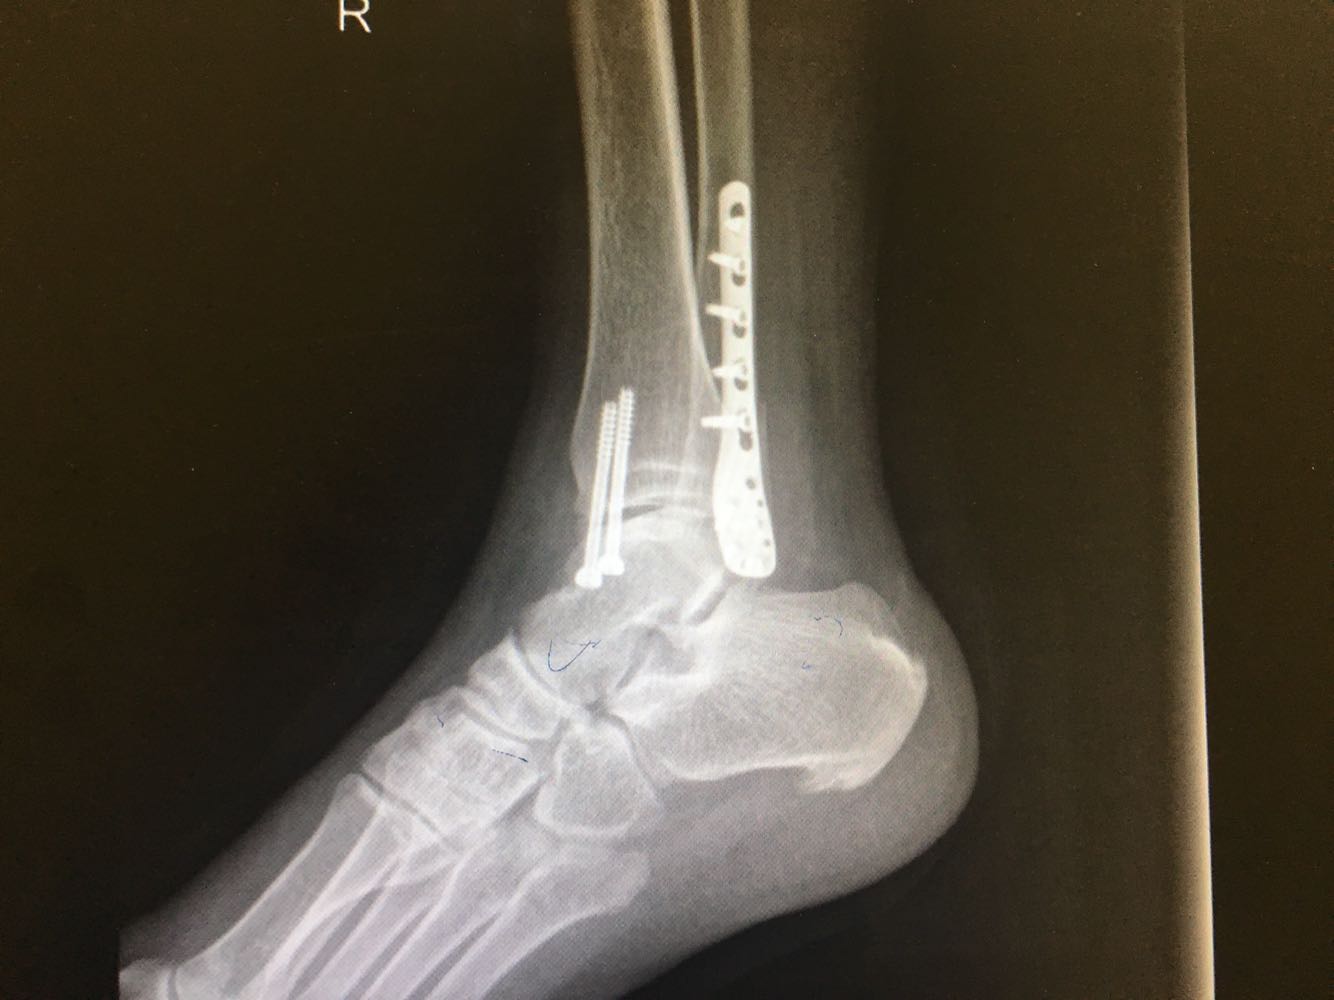

患者,男,54岁。 主诉:外伤致右踝疼痛伴活动受限2天 现病史:患者于2天前不慎扭伤致右踝疼痛,伴活动受限,否认头晕头痛、恶心呕吐等不适,就近医院就诊,查X片示:右踝骨折,予石膏外固定,现为进一步诊治收治入院,发病以来,神清,精神可,胃纳夜眠可,二便无殊,体重无明显变化。

查体:右踝压痛,活动受限,无淤斑淤点,未见皮肤破损,足趾感觉及运动良好。 辅检:右踝部CT

诊断:右侧踝部闭合性骨折 治疗:完善术前检查后行手术内固定